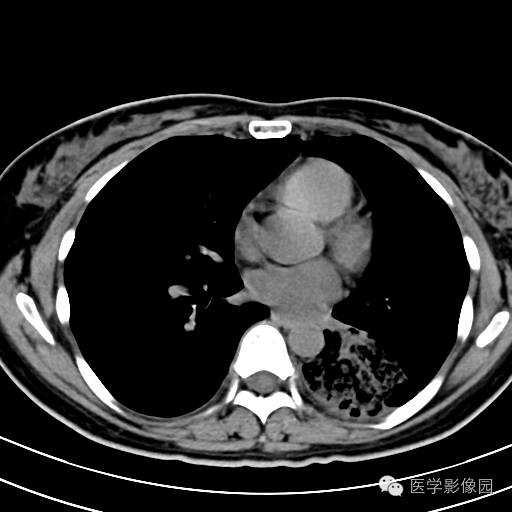

肺叶实变性支气管肺泡癌1例CT影像表现